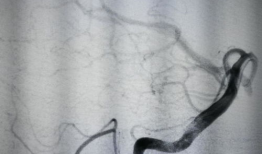

造影视频全过程,揭示血管奥秘与诊疗过程

你知道吗?最近我在网上看到一个超级有趣的造影视频全过程,简直就像是一部迷你电影,让我忍不住想要和你分享一下。这个视频详细记录了整...